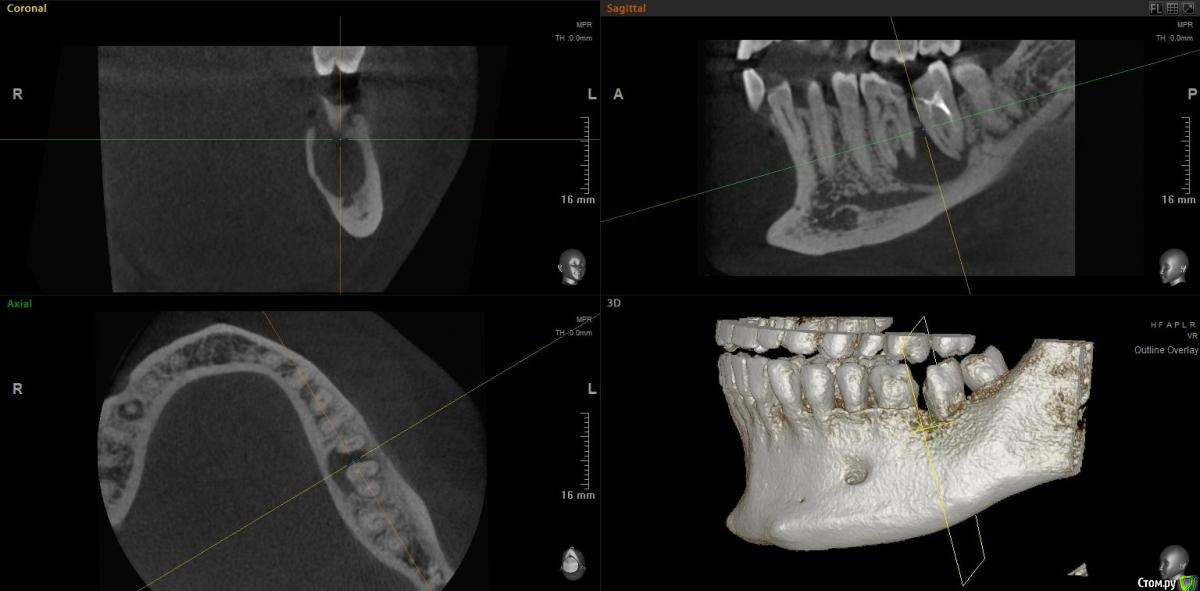

jm3300 Опубликовано 15 ноября, 2020 Поделиться Опубликовано 15 ноября, 2020 Коллеги, можно в данном случае вытянуть консервативно? Ссылка на комментарий

Irouil Опубликовано 15 ноября, 2020 Поделиться Опубликовано 15 ноября, 2020 Тут, похоже, не(только) корневая киста, язычно карман. Вопрос в терапию, наверное, но я скажу - нет 1 Ссылка на комментарий

red_butler Опубликовано 15 ноября, 2020 Поделиться Опубликовано 15 ноября, 2020 Имхо нужно в терапию, по данным срезам не увидел проблем с реэндо 2 Ссылка на комментарий

jm3300 Опубликовано 15 ноября, 2020 Автор Поделиться Опубликовано 15 ноября, 2020 Тут, похоже, не(только) корневая киста, язычно карман. Вопрос в терапию, наверное, но я скажу - нетвозможный карман тоже смущает Ссылка на комментарий

Дмитрий М Опубликовано 15 ноября, 2020 Поделиться Опубликовано 15 ноября, 2020 самого пациента ещё не видел. попросили КТ посмотретьок )) тогда понятноесли только из снимков то 36 пробовать сохранять, эндо и наблюдение а вот 37 больше за удаление был подобный случай, только киста немного меньше была но так же с вовлечением корней 36 и 37 терапевт хотела удалить оба, но решили оставить 36 полечить и наблюдать, а 37(разрушен не подлежал восстановлению) удалил, кисту почистил, ч/з 3 мес имплант. в итоге с 36 все хорошо 1 Ссылка на комментарий